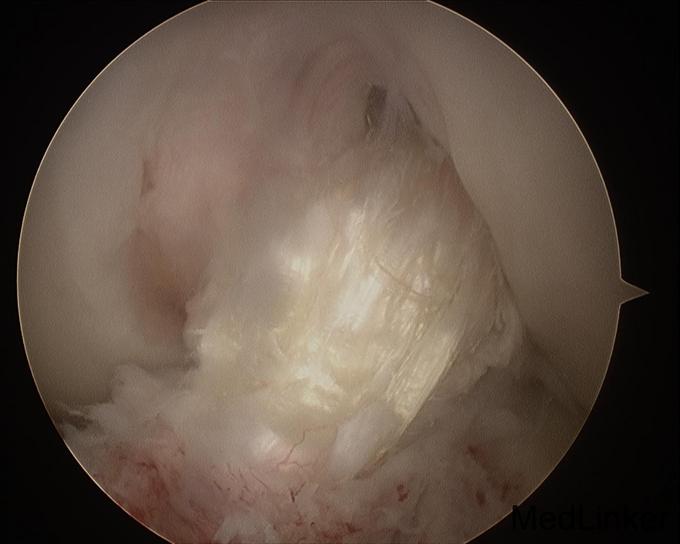

诊断:左膝前交叉韧带重建术后,左膝半月板损伤。 治疗:左膝内固定取出术+左膝关节镜下探查+左膝前交叉韧带皱缩+内侧半月板成形术

随访:患者术后扶拐行走2周。2周后活动度恢复正常,亦恢复正常行走。 讨论:该患者为前交叉韧带自体肌腱重建术后9年,难得有机会进行second look。术中发现重建韧带形态完整,但纤维松散,术前查体亦有松弛现象。术中予以紧缩处理后,术后松弛度明显改善。